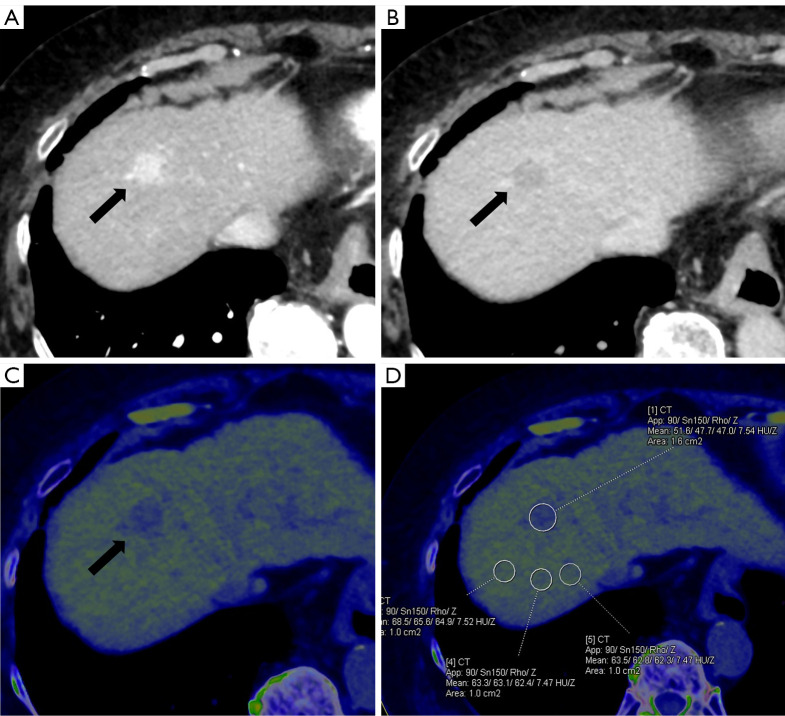

背景:通过非对比双能计算机断层扫描获得的电子密度(ED)的临床应用已被证明可用于脑肿瘤和骨病变的诊断;然而,ED在肝脏中的临床应用尚未得到充分的报道。本研究旨在比较肝细胞癌(hcc)、肝转移瘤、肝血管瘤和肝囊肿之间的ED,并评估ED在恶性肿瘤和良性病变之间的鉴别诊断价值。方法:89例患者,男53例,女36例,平均年龄67.2±13.2岁。测量24例hcc、19例肝转移、28例肝血管瘤和18例肝囊肿的EDs。计算经背景肝实质ED归一化后的相对ED (rED)。对局灶性肝病变(FHLs)的ED和rED进行统计学分析。采用受试者工作特征曲线分析评价ED和rED在鉴别恶性肿瘤与良性病变中的诊断价值。结果:ED和rED在恶性肿瘤中高于良性病变。结论:ED有助于FHLs的鉴别诊断。rED的使用进一步提高了诊断性能。

Background: The clinical utility of electron density (ED), obtained by non-contrast dual-energy computed tomography, has been demonstrated for the diagnosis of brain tumors and bone lesions; however, the clinical utility of ED in the liver has not been adequately reported. This study aimed to compare ED between hepatocellular carcinomas (HCCs), liver metastases, hepatic hemangiomas, and hepatic cysts and assess the differential diagnostic performance of ED between malignant tumors and benign lesions.

Methods: Eighty-nine patients (53 men and 36 women; mean age, 67.2±13.2 years) were included. EDs were measured for 24 HCCs, 19 liver metastases, 28 hepatic hemangiomas, and 18 hepatic cysts. The relative ED (rED), normalized by the ED of the background liver parenchyma, was calculated. The ED and rED of the focal hepatic lesions (FHLs) were statistically analyzed. Receiver operating characteristic curve analysis was used to evaluate the diagnostic performance of ED and rED in differentiating malignant tumors from benign lesions.

Results: The ED and rED were higher in malignant tumors than in benign lesions. Significant differences in ED were observed among all lesions (P<0.05) except liver metastases and hepatic hemangiomas. Significant differences in rED were observed among all lesions (P<0.05) except HCCs and liver metastases. The area under the curve of rED for distinguishing between malignant tumors and benign lesions was significantly larger than that of ED (0.88 vs. 0.80, P<0.05).

Conclusions: ED aids in the differential diagnosis of FHLs. The use of rED further improves diagnostic performance.